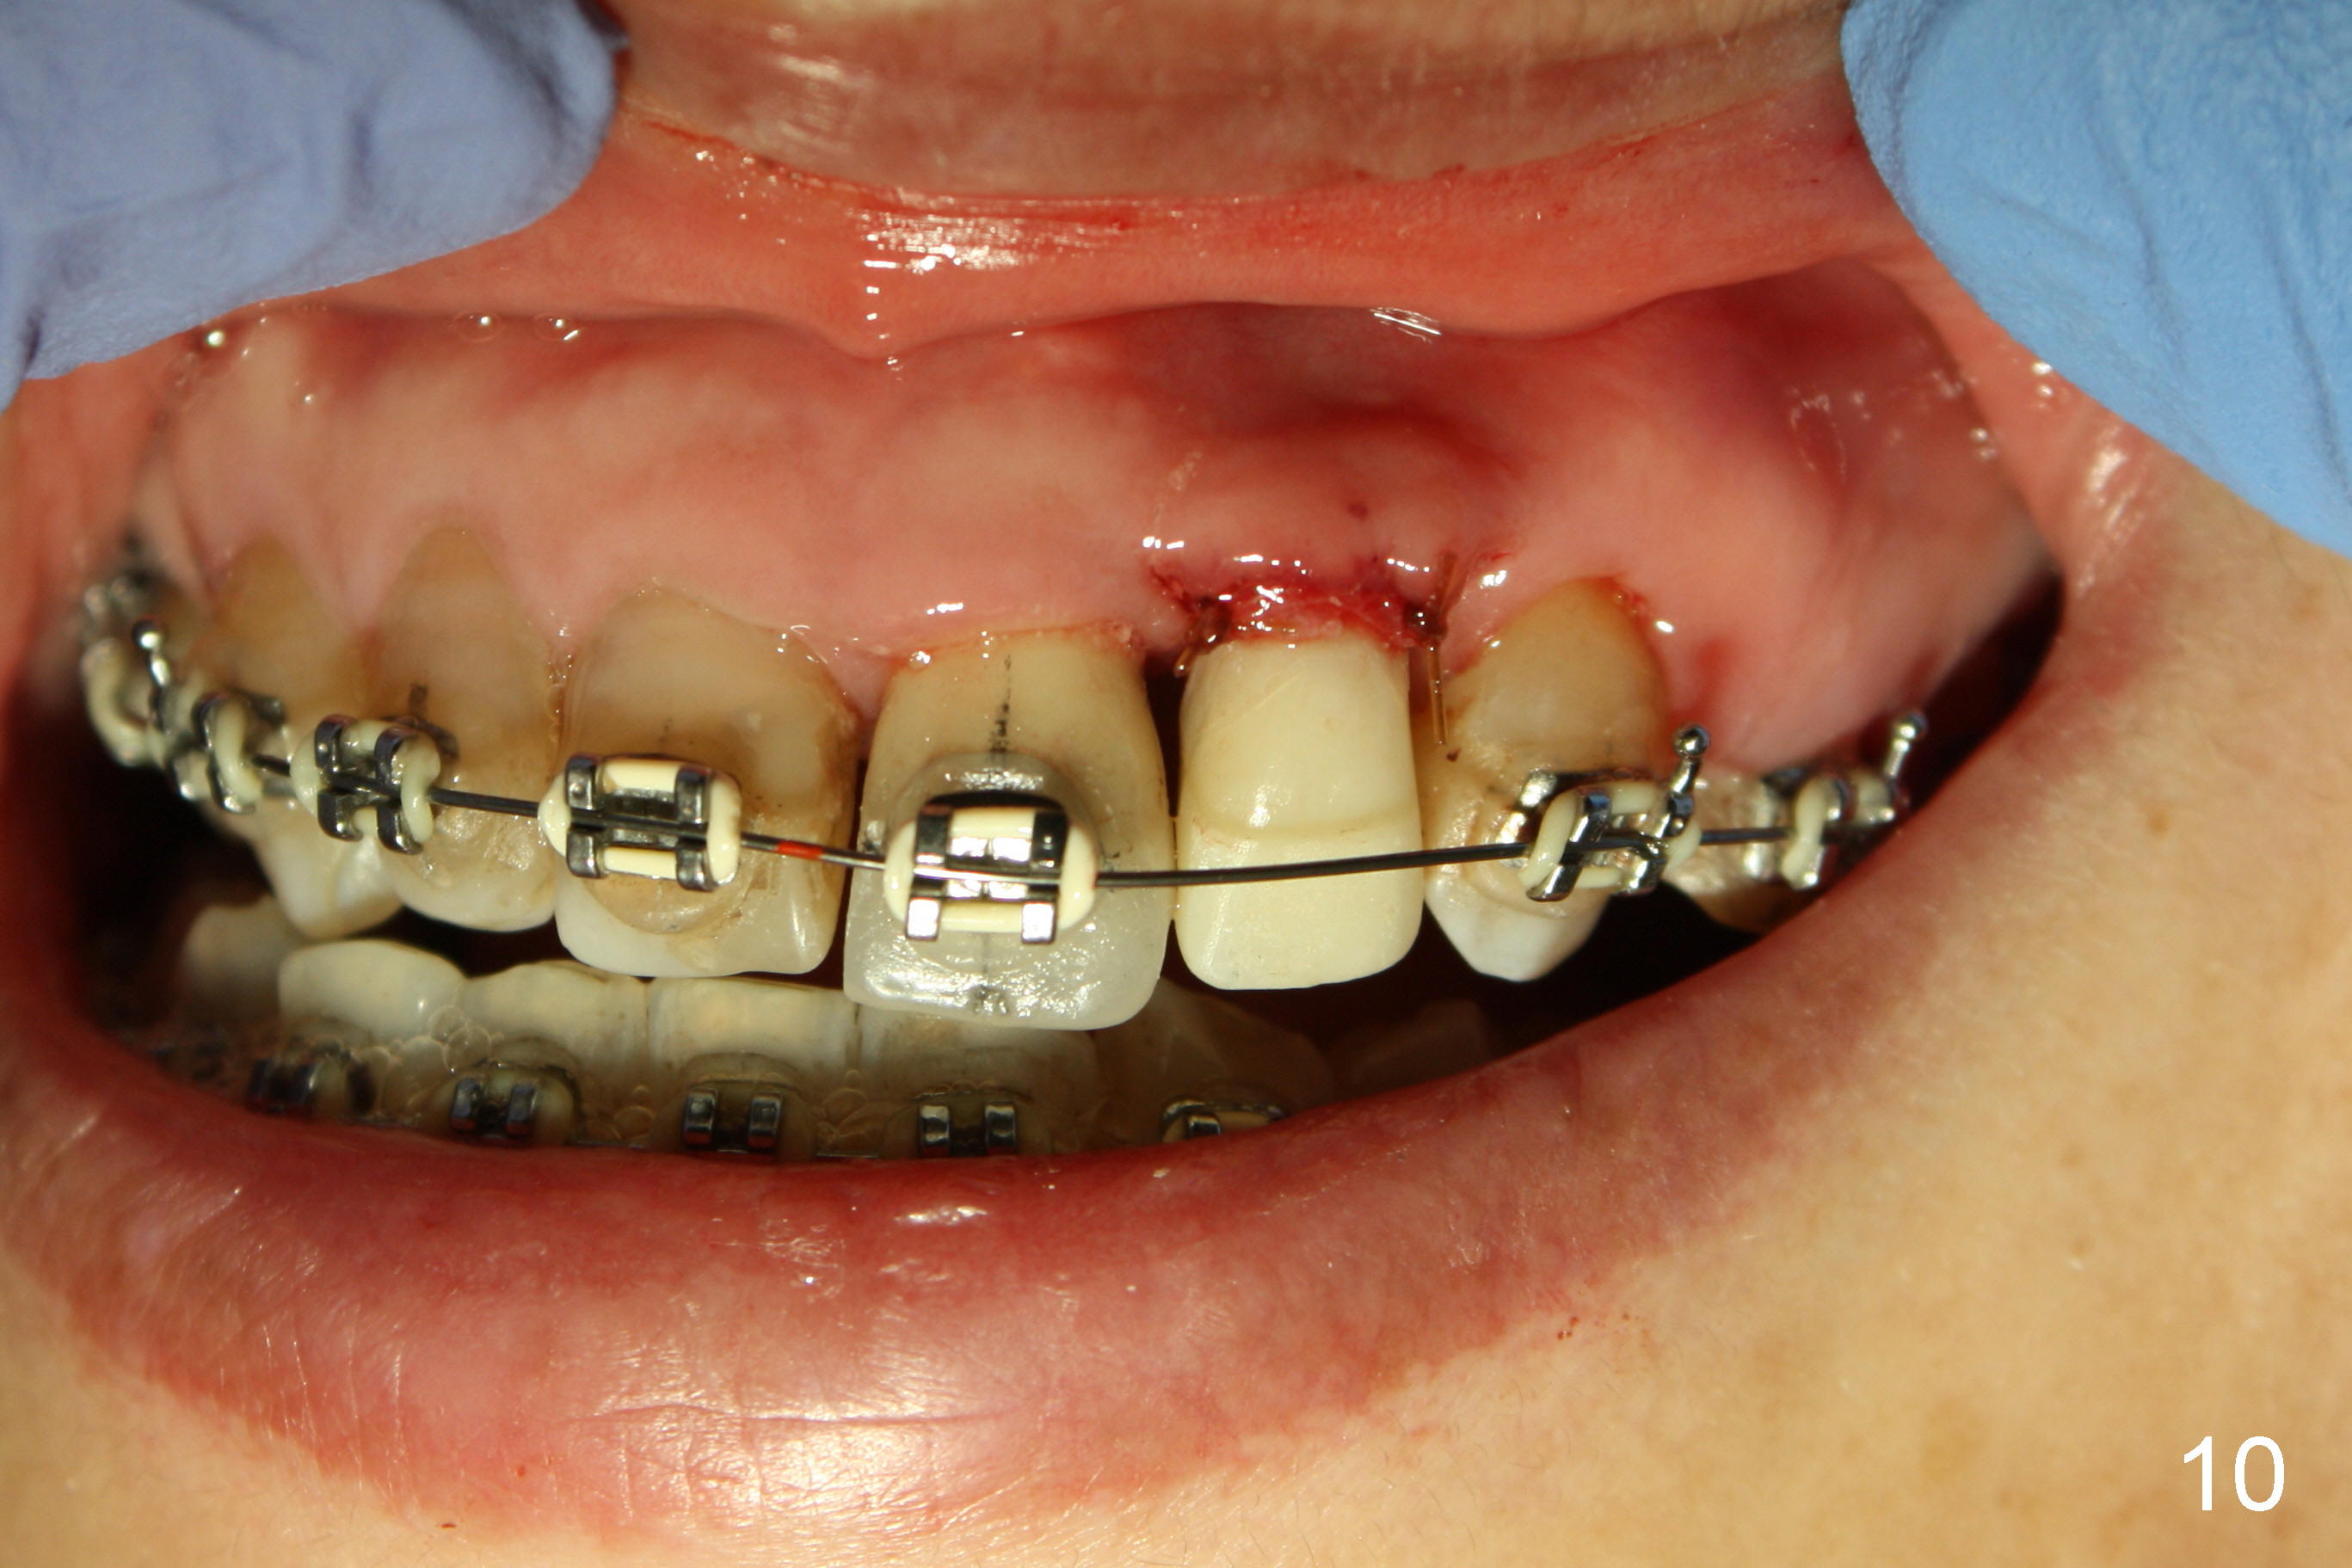

A prominent feature of implant failure in this case is pain. The patient feels that the pain is from the base of the nose. PA taken 3 days postop shows that the implant is inferior to the nasal floor (Fig.2 red ^). Clinically, the buccal gingiva continues to be erythematous 10 days postop (Fig.1). The pain is so unbearable that the implant (3.8x14 mm) is removed 10 days post placement. After repeated debridement, a 4.1 mm tap (Fig.3 T) is manually inserted with torque. A 4.1x14 mm submerged implant is placed with insertion torque < 30 Ncm, but it is placed subcrestally (Fig.4 <--). This time an immediate provisional is not provided. The flap is sutured. The pain disappears immediately. No infection is found 7 days postop (Fig.5). However, an asymptomatic vesicle is noted at the crest 3 weeks postop (Fig.6). The gingiva looks normal 2 and 3 months postop (Fig.7,8). The coronal gap dissolves 3 months postop (Fig.9 >, as compared to Fig.4), suggesting osteointegration. The implant is uncovered 4 months postop (Fig.10). Bracket is placed 5 months postop (Fig.10'). One month later, the left central incisor improves in position coronocervically (Fig.11), but the overjet needs correction by distalization of the upper anterior teeth. The implant at the site of #10 may be used as an anchorage.